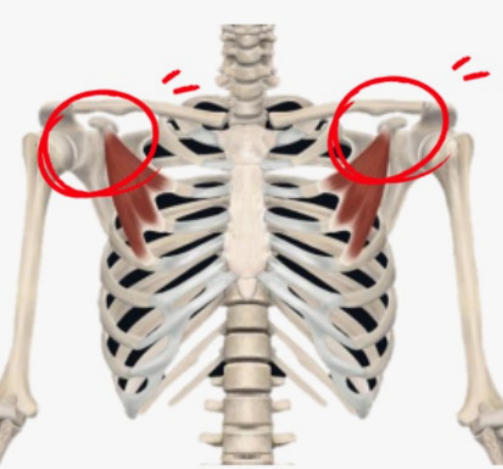

안녕하세요, 여러분! 요즘 어깨 통증으로 인해 일상생활이 불편하시지는 않나요? 50견(오십견)은 어깨 관절의 유착으로 인해 발생하는 질환으로, 초기에는 가벼운 통증이지만 점차 팔을 올리거나 뒤로 젖히는 것이 힘들어질 수 있습니다. 저도 한때 팔을 들어 올리기조차 어려웠던 경험이 있어서 그 고통을 잘 알고 있습니다. 하지만 다행히도 꾸준한 스트레칭을 통해 어깨의 가동 범위를 회복하고 통증을 완화할 수 있습니다. 오늘은 50견을 극복하는 데 효과적인 스트레칭 방법을 소개해 드릴 테니, 함께 건강한 어깨를 되찾아 봅시다!

시계추 스트레칭은 어깨 관절을 부드럽게 풀어주고 통증을 완화하는 기본적인 운동입니다. 이 동작은 어깨 관절의 유연성을 회복하는 데 도움을 줍니다.